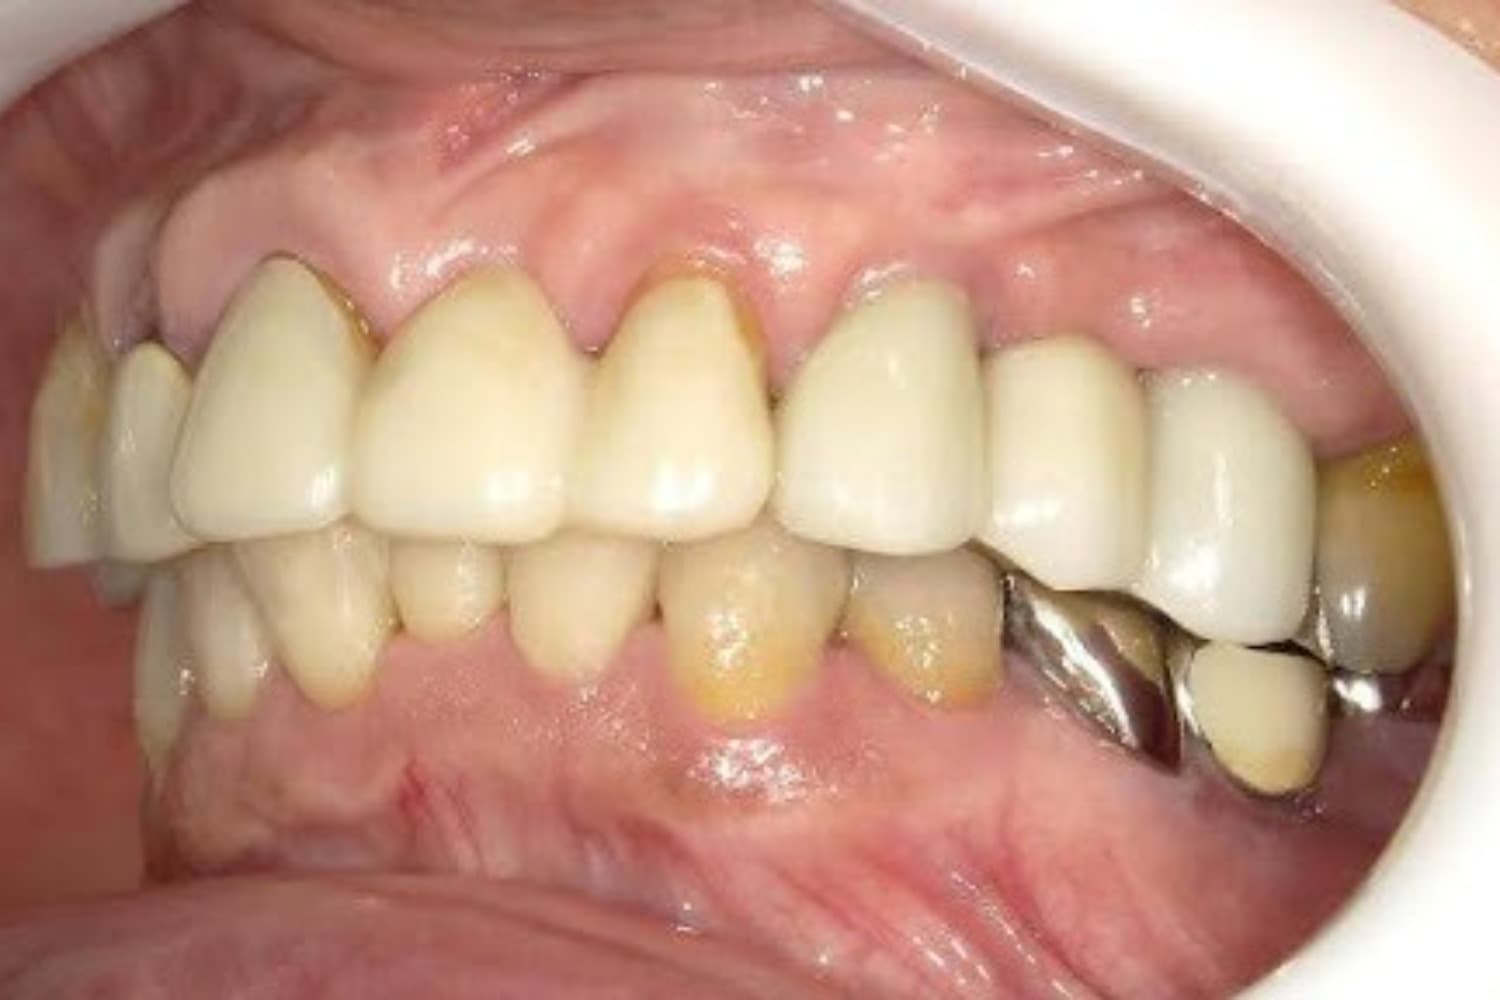

左上の歯のインプラント治療(60代女性)

After

インプラント抜歯即時埋入・即時荷重(抜歯と同時にインプラントを埋入し、当日に仮歯を入れる)

60代

女性

重度の歯の動揺があり、何もしていなくとも痛みがある。治療にあたって前歯がないことを気にする。

4ヵ月

10回

814,000円(税込) 費用の内訳: 【インプラント基本料】330000円×2=660000円(税込み) 基本料金に以下を含む ・フィックスチャー及び手術費用 ・投薬費用、 ・レントゲン費用 ・インプラント上部費用(アバットメントおよびジルコニアクラウンの費用用) 【オプション費用】 ・右上5グラフトレスサイナスリフト費用 33000円(税込み) ・右上3抜歯即時荷重費用 33000円(税込み) ・暫間インプラント費用 0円